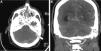

Caso clínicoSe trata de un varón de 37 años que acudió al hospital por un cuadro de cefalea de inicio subagudo, hipoestesia transitoria del brazo izquierdo y pérdida súbita de consciencia. La tomografía computarizada cerebral (TC) mostró una hemorragia subaracnoidea focal frontal derecha (fig. 1) pero la angio-TC y el estudio arteriográfico no mostraron alteraciones. Seis meses después, el paciente presentó un episodio de cefalea y mareo, por lo que consultó de nuevo a nuestro centro. Se realizó otra angio-TC que demostró la presencia de estructuras vasculares anómalas en la fosa posterior y una irregularidad en el seno sigmoideo acompañado de ingurgitación de las ramas de la arteria carótida externa (fig. 1). La nueva arteriografía cerebral reveló la presencia de 2 FAVD: una en la fosa posterior con aferencias de las arterias carótidas interna y externa con drenaje venoso a través de los senos sigmoideo y transverso, y venas corticales (tipo a + b de la clasificación de Cognard II)8, y la segunda incluía el seno sagital superior, con aferencia de la arteria meníngea izquierda y reflujo venoso cortical (Cognard III) (fig. 2). La resonancia magnética cerebral (RM) con venografía mostró la presencia de trombosis del seno transverso izquierdo.